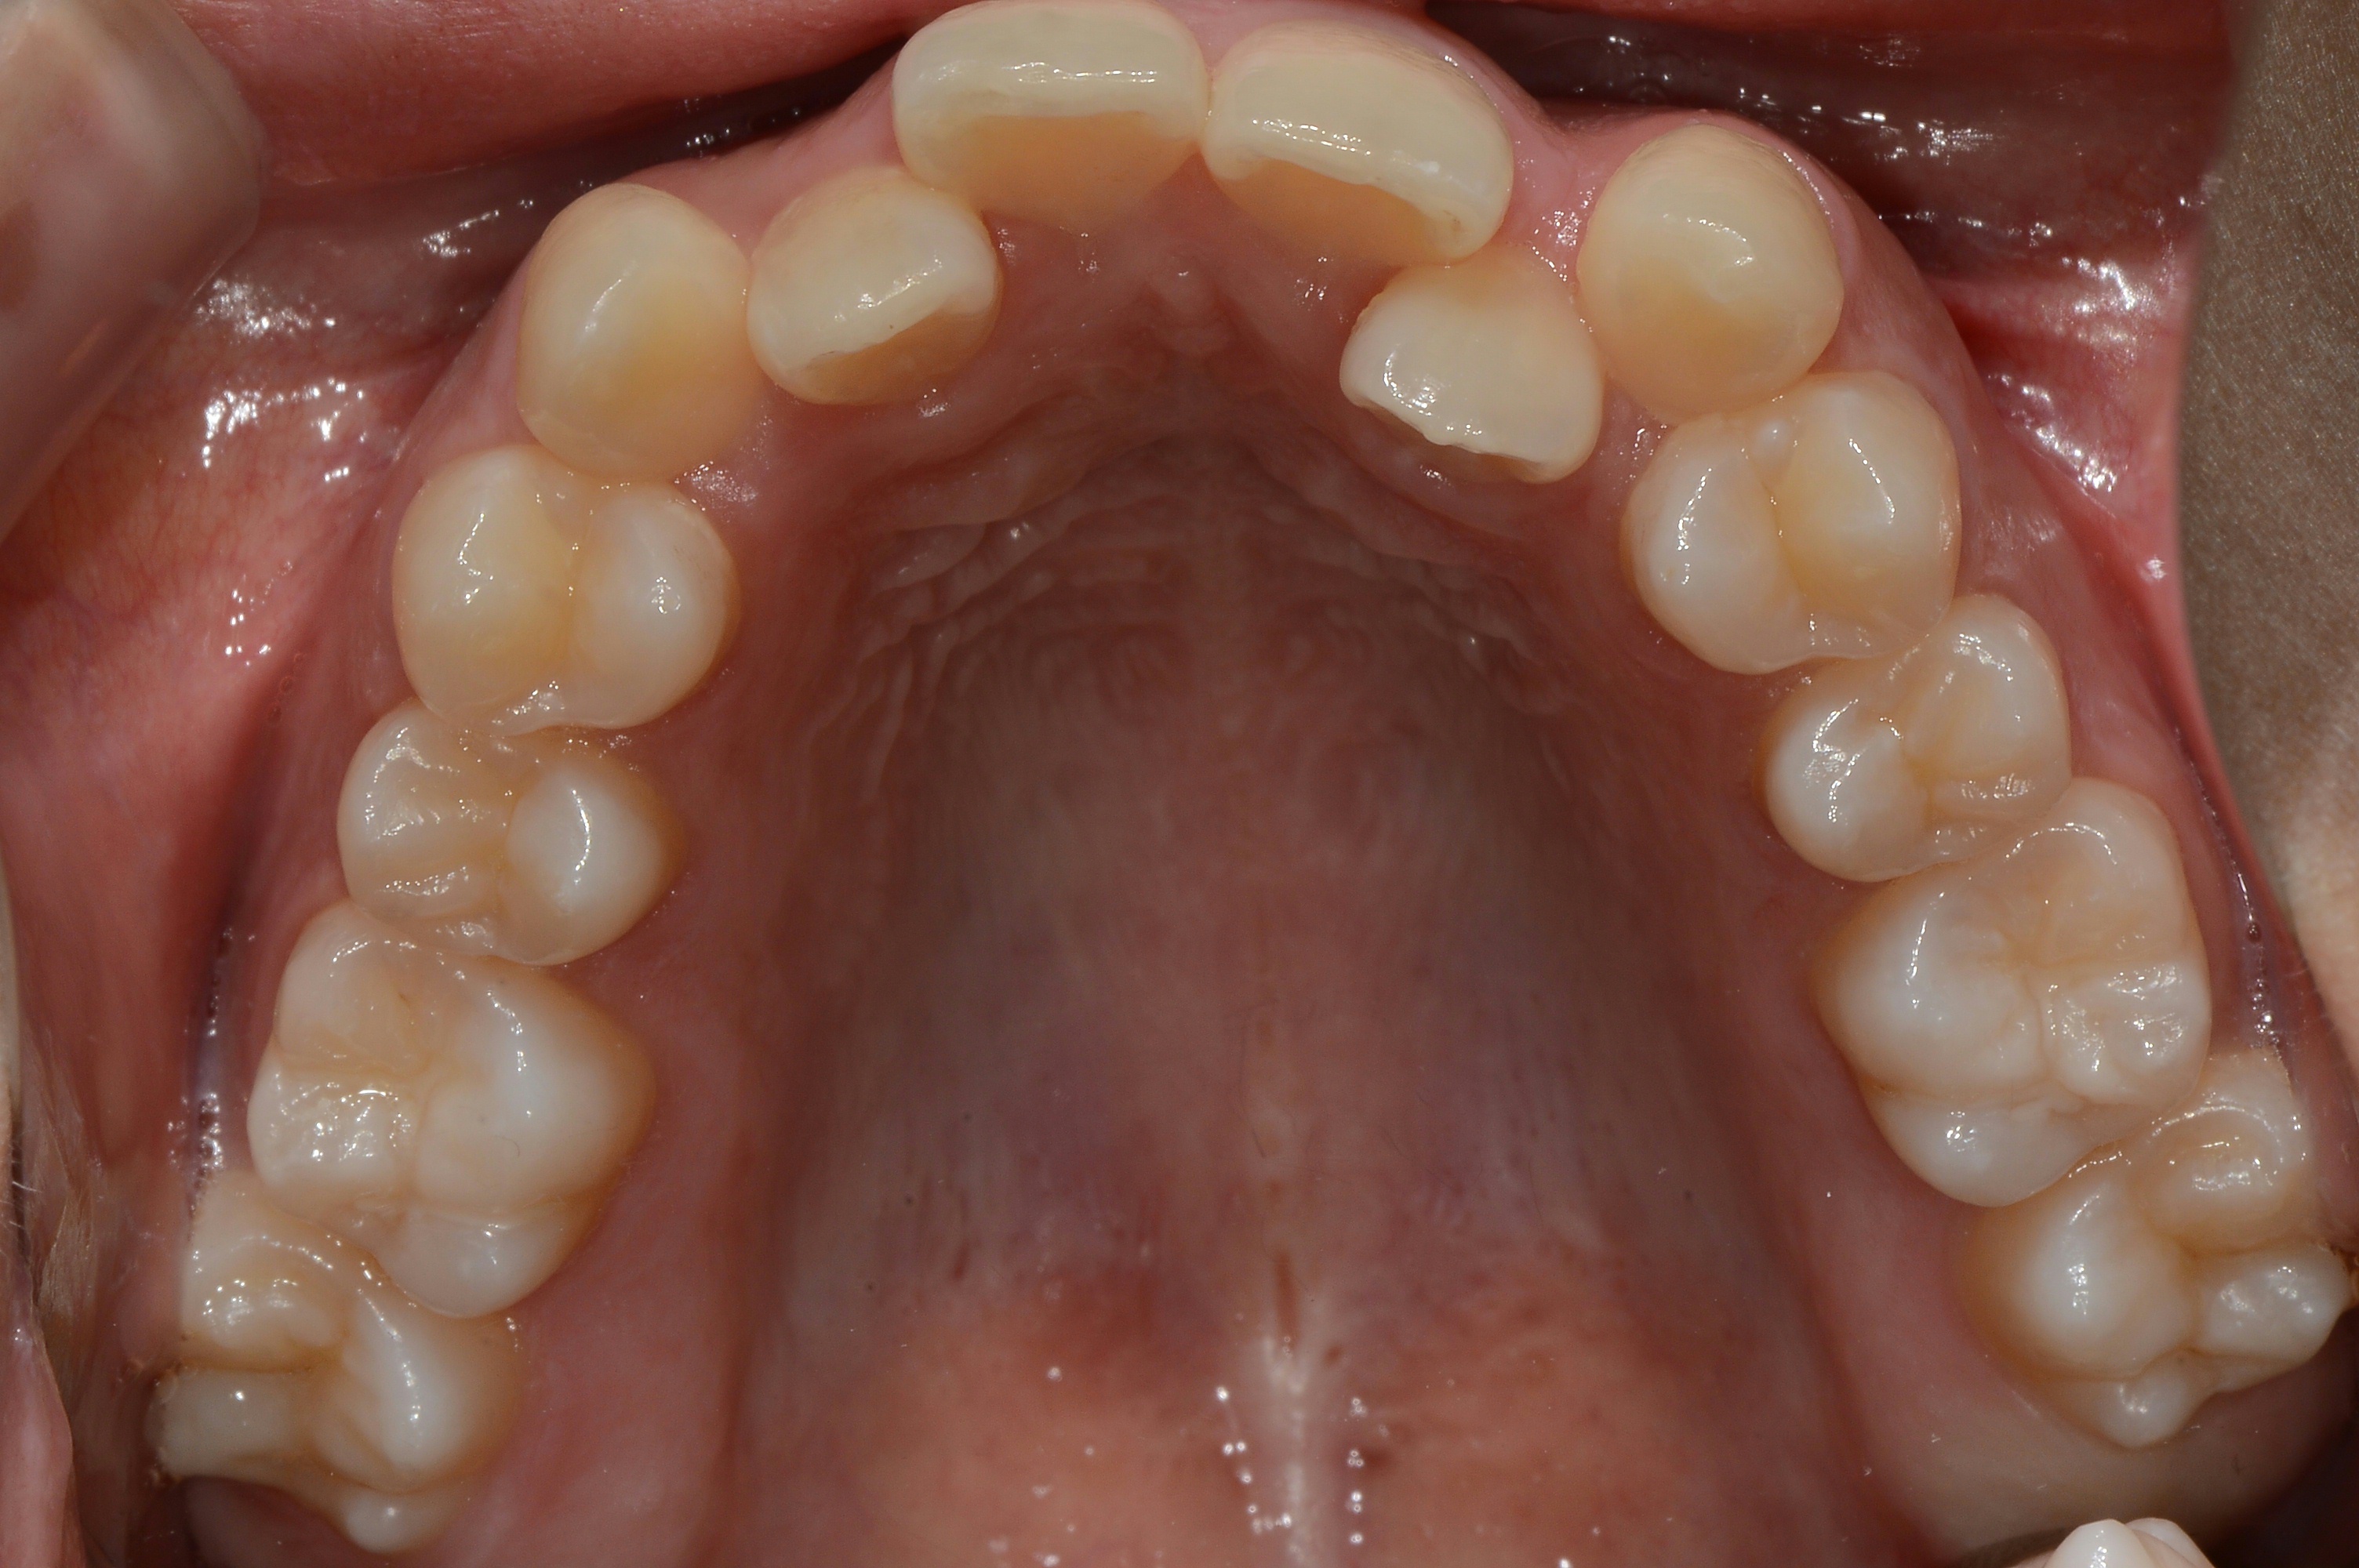

치료 전 사진입니다.